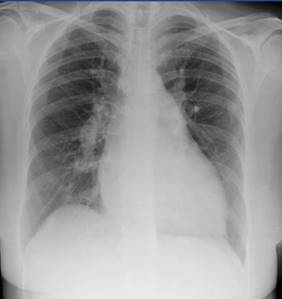

Imagen 1

Rx de Tórax

Reporte: No se aprecia el colapso pulmonar. No enfisema. No signos infiltrados micronodulares. No derrame pleural. No borramiento de ángulos costofrénicos. No Líneas de Kerley.